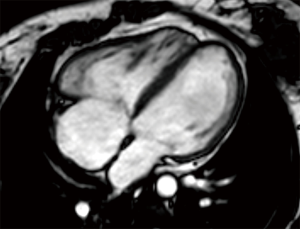

In clinical practice, CMR’s principal advantage over TTE is the accurate quantification of biventricular size and function, and it is the gold standard for volume and flow assessment in TOF (12) (Figure 3). Optimal timing for PV replacement in PR is challenging, and current recommendations rely on RV volumes, which are performed with cine steady-state free precession (SSFP) sequences. Generally, PV replacement should be indicated before reaching an RV end-diastolic indexed volume of 160 mL/m2 or an RV end-systolic indexed volume of 80 mL/m2 (10,22). These are CMR thresholds considered a point of no return beyond which RV function and reverse remodeling recovery would be expected to be limited after PV replacement (23,24). On the other hand, intervening too early potentially exposes patients to reinterventions later in life. Consequently, since the indication for PV replacement depends on CMR, it should be indicated in all patients prior to deciding intervention. Cine sequences also allows us to assess RVOT wall motion and geometry, including obstruction to flow, detect valvular regurgitation and stenosis (Figure 4) and residual shunts, and evaluate aortic dilatation.

In most patients 2D TTE is insufficient for effectively evaluating the complex, nonstandard, retrosternal shape and function of the RV. 3D echocardiography overcomes this limitation and is accurate and reproducible for assessment of both RV volumes and function; furthermore, it is feasible in up to 90% of patients, with high correlation to CMR values (15,16). Hence, 3D echocardiography RV volumes and EF are now preferred over 2D measurements (8). However, this technique requires software and equipment that aren’t widely available (15).